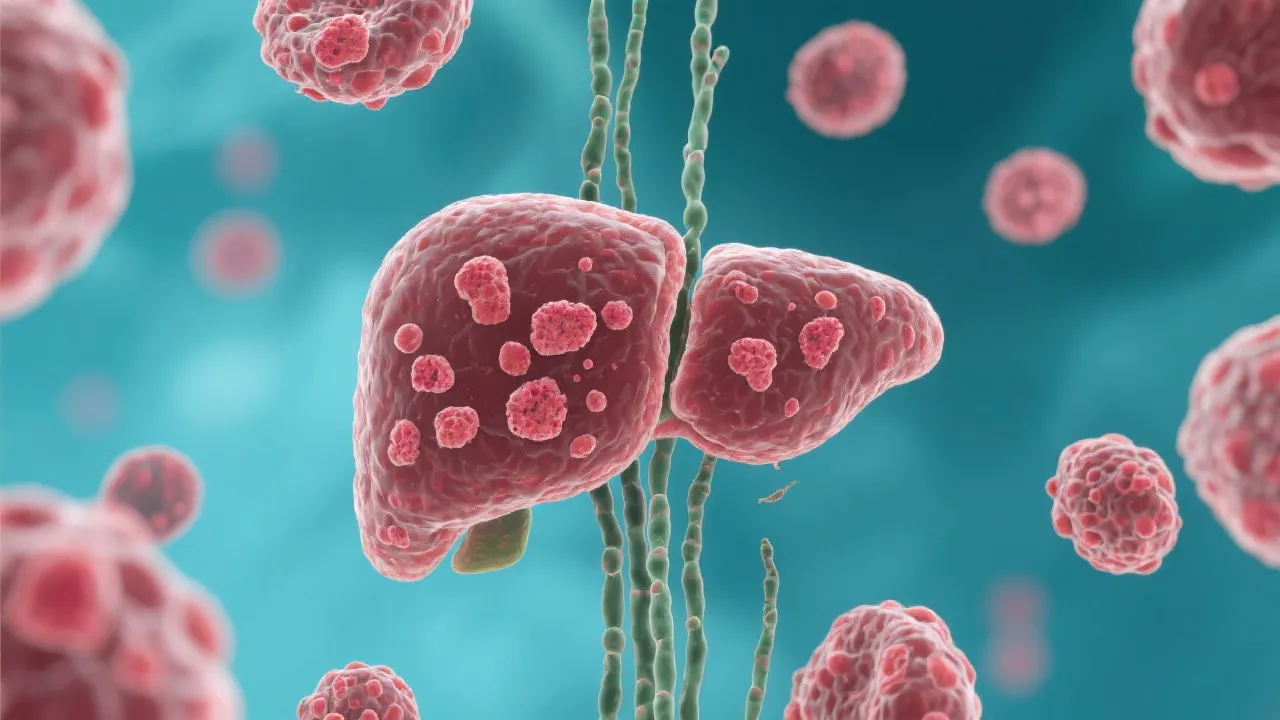

Understanding Hepatitis E and Liver Transplant

Understanding Hepatitis E and Liver Transplants

Understanding Hepatitis E and Liver Transplants

Understanding Hepatitis E and Liver Transplants

Understanding Hepatitis E and Liver Transplants

Hepatitis E and Liver Transplant

Understanding Hepatitis E and Liver Transplant

Understanding Hepatitis E and Liver Transplants

Navigating Hepatitis E and Liver Transplant

Navigating Hepatitis E Liver Transplants

Hepatitis E and Liver Transplant Insights

Hepatitis E and Liver Transplant